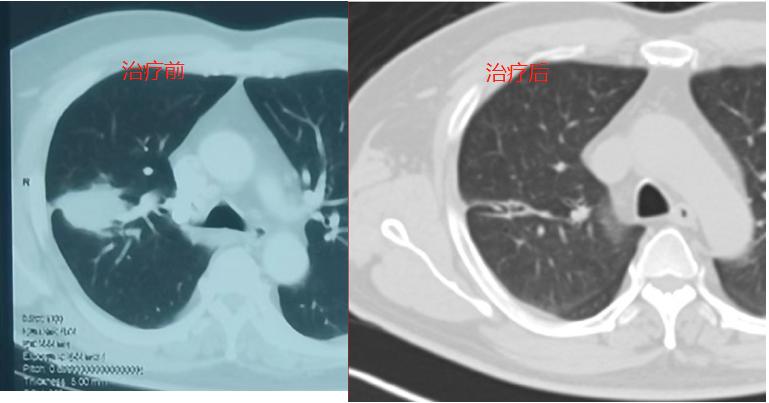

06.类似病例

下面是一例三期肺癌通过靶向治疗病灶明显好转的情况。

治疗后明显缩小